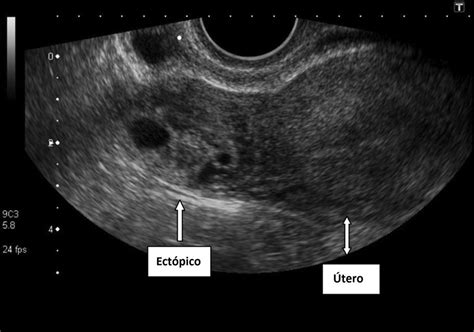

La ecografía es una herramienta crucial para confirmar la sospecha clínica:

- Ecografía transvaginal: Es de gran utilidad y proporciona imágenes más detalladas. Permite visualizar una masa anexial que contiene un saco ovular con trofoblasto y, en ocasiones, un embrión con latidos cardíacos (en el 20% de los casos). Signos ecográficos indirectos incluyen la ausencia del saco gestacional en el endometrio, una masa anexial próxima al ovario, el movimiento independiente de esta masa respecto al ovario, el "anillo tubárico" (anillo hiperecoico alrededor de la masa) y el patrón trilaminar. Sin embargo, en un 26% de los casos, la ecografía transvaginal puede ser normal a pesar de la presencia de un embarazo ectópico.